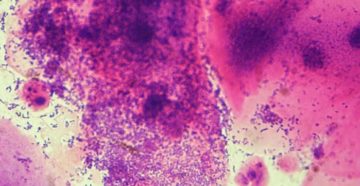

Гарднерелла: лечение Гарднерелла или гарднереллез–это женское заболевание. Возбудителем заболевания принято считать микроорганизм гарднереллу вагиналис. По…